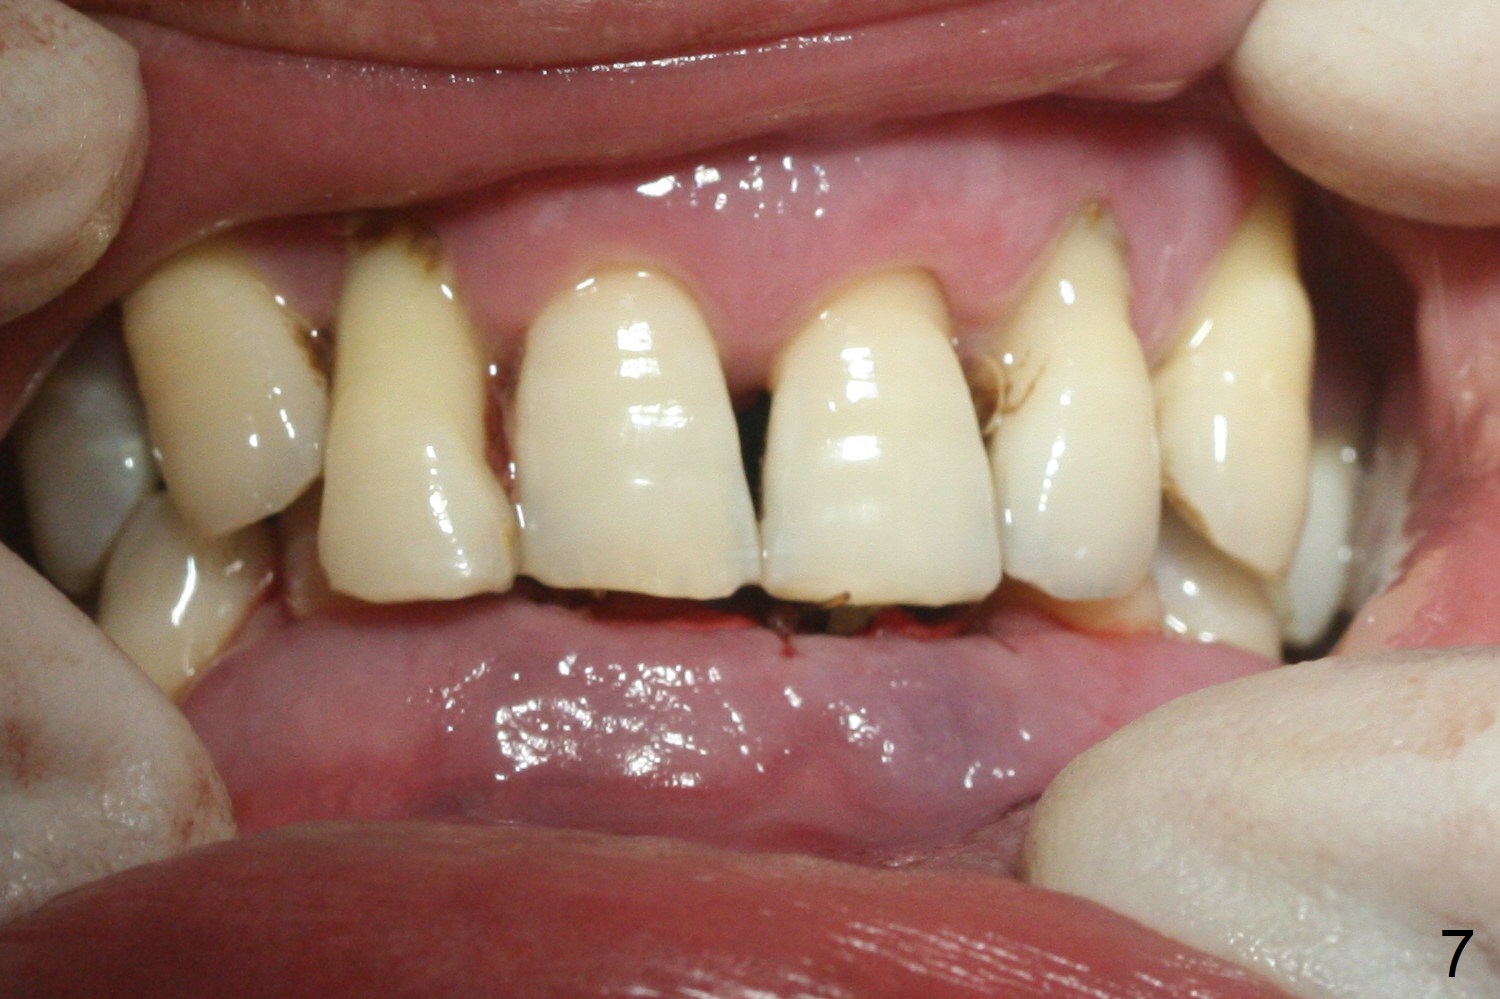

After extraction of 4 of the lower incisors, there are basically 2 sockets (#23/24 and 25/26), separated by the apparently midline bone (Fig.1 red line). In spite of using Lindamann bur to move the 25/26 osteotomy mesially, a 3x14(2) mm dummy implant remains close to the tooth #27 (Fig.2). The terminal branch of the Incisive Canal (<) is located between the lateral and central incisors. A de novo osteotomy (Fig.3 (1.5 mm drill)) is made mesial to the original one (O). While the 3x14(2) mm dummy implant is incompletely placed at #25/26, a 3x14(4) mm 1-piece one is placed at #23/24 (Fig.4). Finally the same implant is placed at #25/26 with placement of mineralized cortical/cancellous bone (Fig.5 *). When the large sockets are sutured, the supraerupted teeth #7-9 touch the lower gingiva (Fig.6). The incisal edge is reduced for clearance (Fig.7). Periodontal dressing is less likely to be dislodged with the incisal edge reduction (Fig.8,9). A provisional FPD is fabricated 1 week postop. Hard (Fig.10) and soft (Fig.11,12) tissues heal 5.5 months postop. The patient returns for crown cementation 3 months post impression (9 months postop, Fig.13,14).